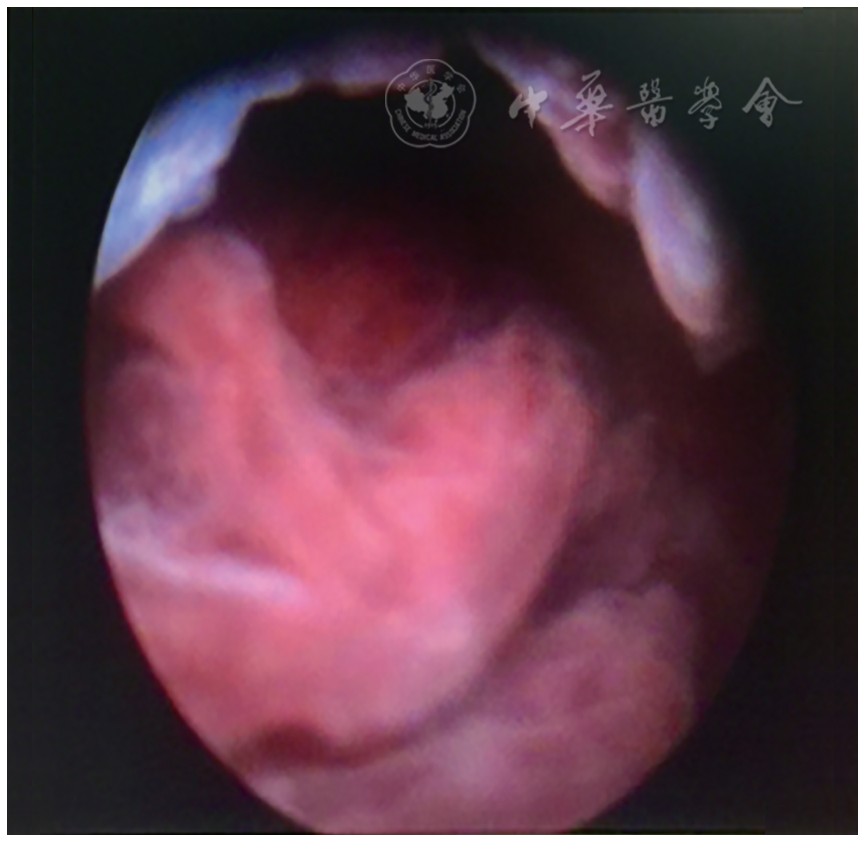

宫腔镜下子宫穿孔图片,腹腔镜下子宫穿孔图片

图2 宫腔镜下子宫右侧壁输卵管嵌顿

子宫穿孔